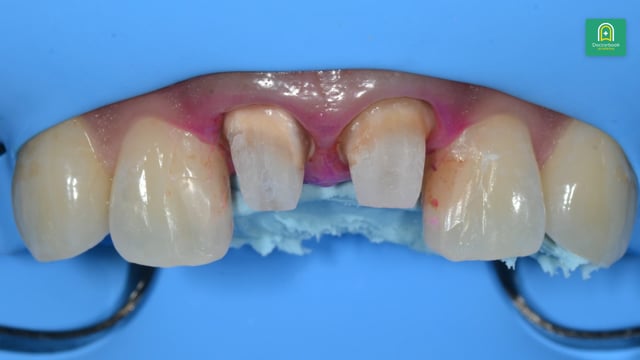

前歯部の審美症例のプレゼンテーション。審美修復を行う際の診査診断および治療計画についての動画です。症例:37歳女性、前歯の色が気になる再生する

土屋先生による審美修復についての参考症例を見ていきます。プロビジョナライゼーションによる審美修復の診査診断と実際の手技について詳しく解説いただきます。再生する